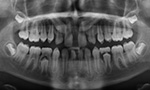

Um das genaue Ausmaß zu bestimmen, fertigt der Kieferorthopäde aus Abformungen des Ober- und Unterkiefers ein Gebissmodell an.Eine Panoramaröntgenaufnahme liefert Informationen über alle Zähne. Zusätzlich wird ein Fernröntgenseitenbild des Schädels erstellt. Damit können Größe, Form und Wachstumsrichtung des Ober- und Unterkiefers und deren Lage zueinander bestimmt werden.